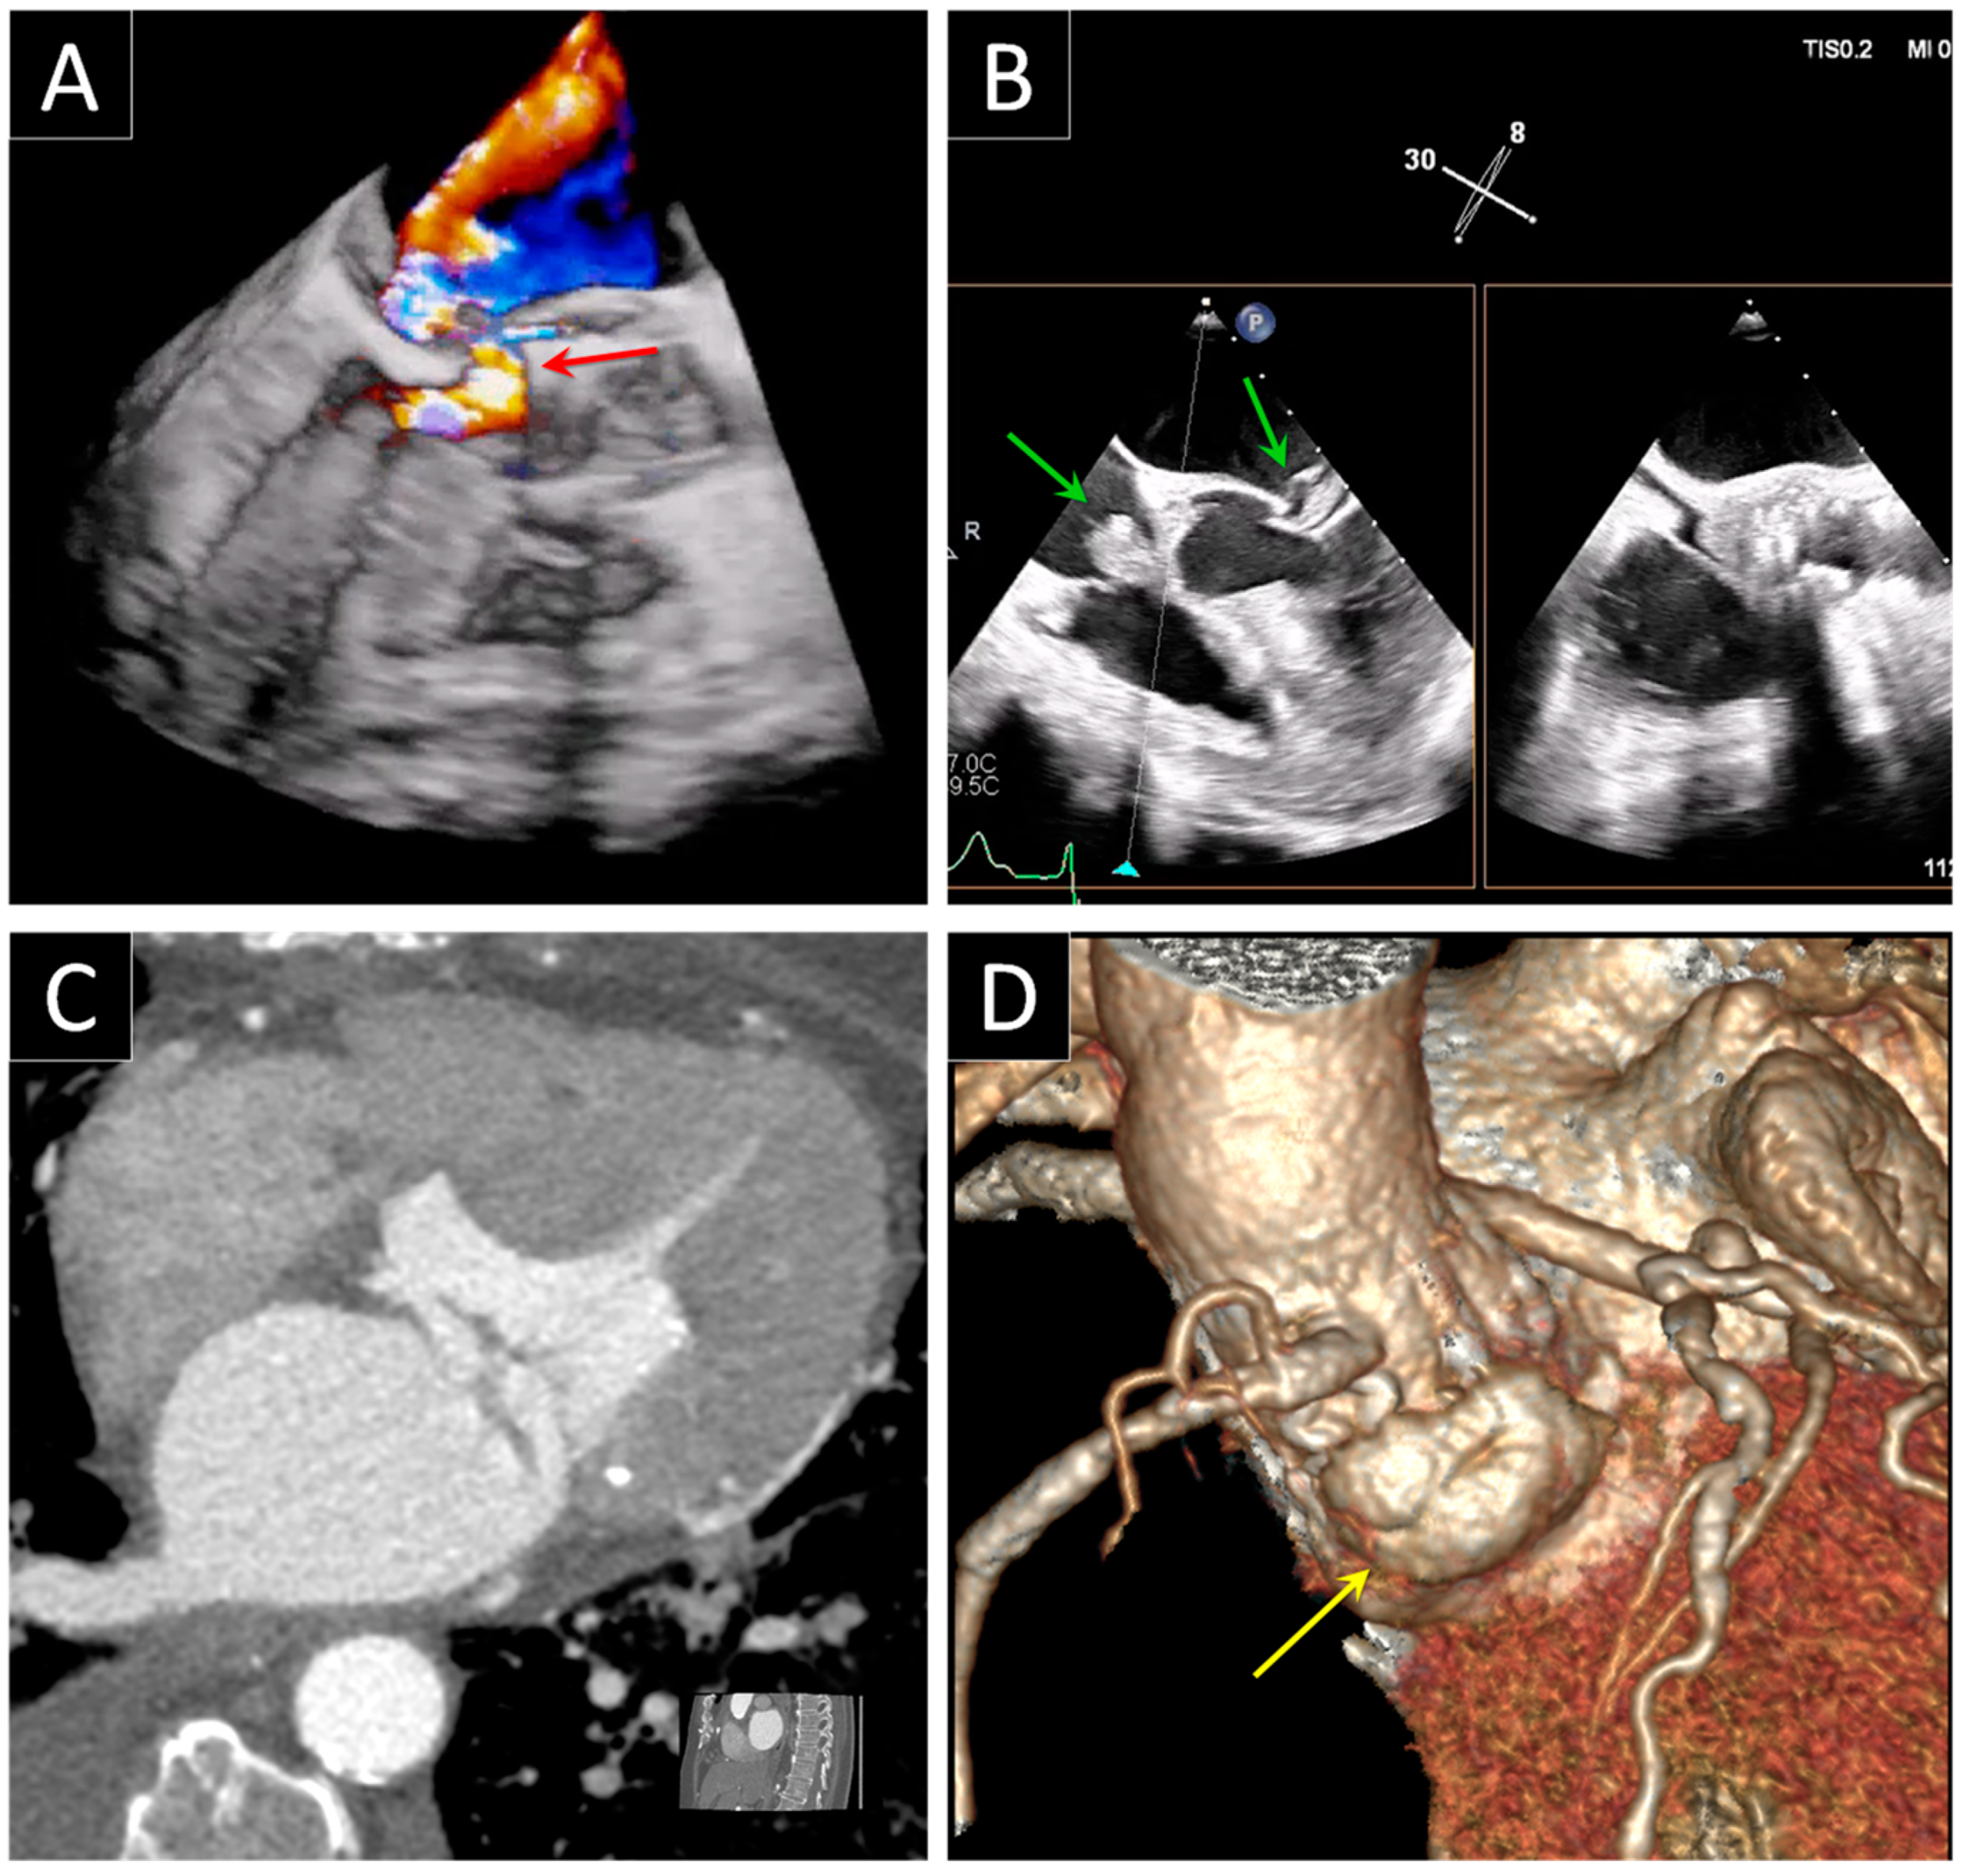

5. Prosthetic Endocarditis